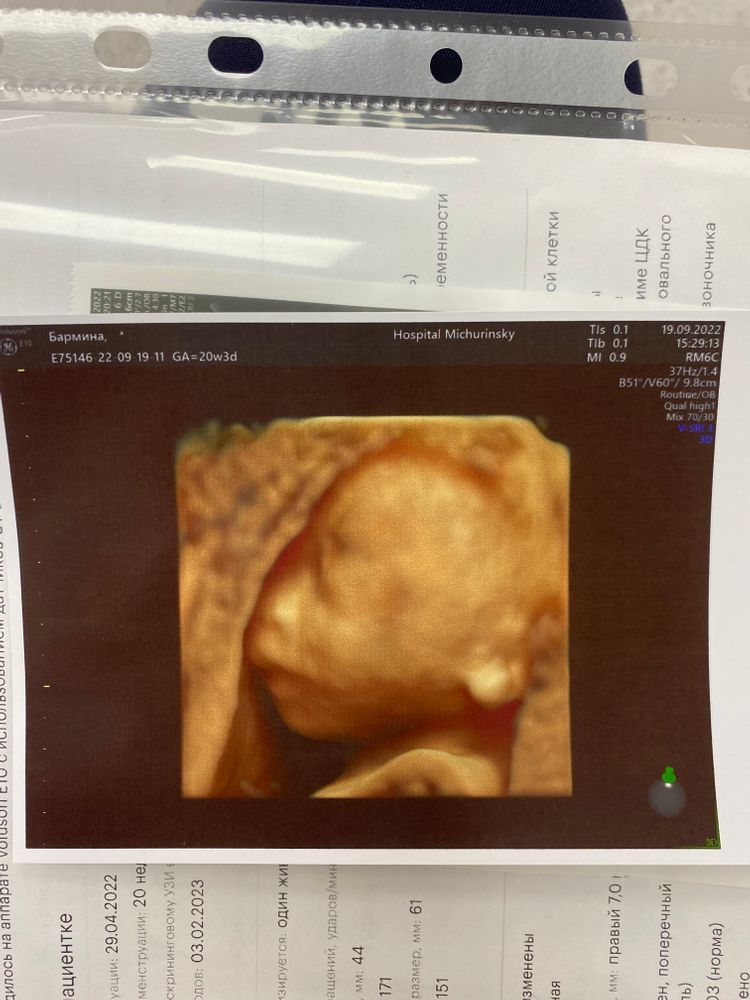

Лена, по первому скринингу 20 ровно, а по мес 20+3

Аня , ну вот для сравнения у меня был скрининг в 20+4 по акуш (19+4 по 1му скринингу), вес плода 305г. Изображение А до этого было УЗИ в 19+3 по акуш (18+3 по 1ма скринингу), вес был - 227г. Получается в среднем за 1 день +10г в весе)) на этом сроке😉👌🏻

Лена, вот мое Изображение